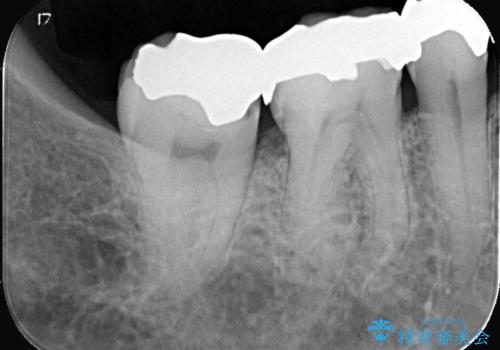

- メンテナンスで虫歯が見つかり、治療を行いました。

まず既存の銀歯を除去し、虫歯を取り除いた後、オールセラミッククラウンで修復しました。

銀歯の下は、目に見えないうちに虫歯が進行していることがよくあります。

特に古くなった銀歯や、咬み合わせの圧力で微細な隙間ができた場合にリスクが高くなります。

また、銀歯には微量の金属(銀や銅、水銀など)が含まれており、長く口の中に入れておくことで金属イオンが溶け出すことがあります。